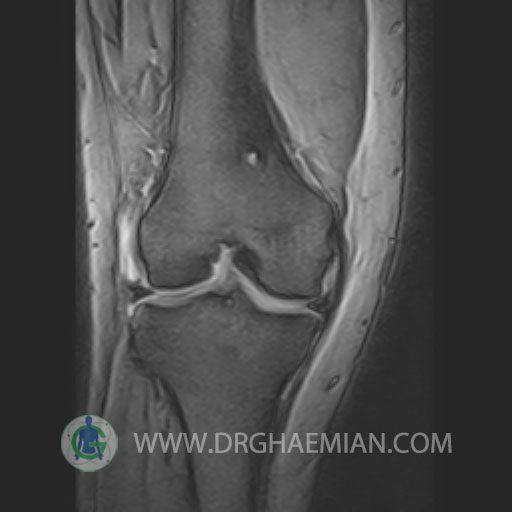

RIGHT KNEE MRI

(Without contrast)

Technique: Sagittal T1, T2 , Axial GE , coronal & sagital fatsat .

The bones comprising the knee joint are normal in configuration.

The cortical bone has normal thickness.

The hyaline cartilage covering patella, fermoral condyles and tibial plateau shows normal signal and thicknees.

PCL ,MCL & LCL are intacted.

Patellar ligamentum and quadriceps tendon are normal in shape and signal intensity .

– Knee joint effusion with soft tissue swelling around the knee

– Grade 2 signal change in P.H. of medial meniscus with partial tearing of posterior root & meniscal extrusion

– Grade 2 signal change in P.H. of lateral meniscus with meniscal extrusion

– Complete tearing of ACL ( femoral detachment ) with bone bruise in plateau of tibia

are seen